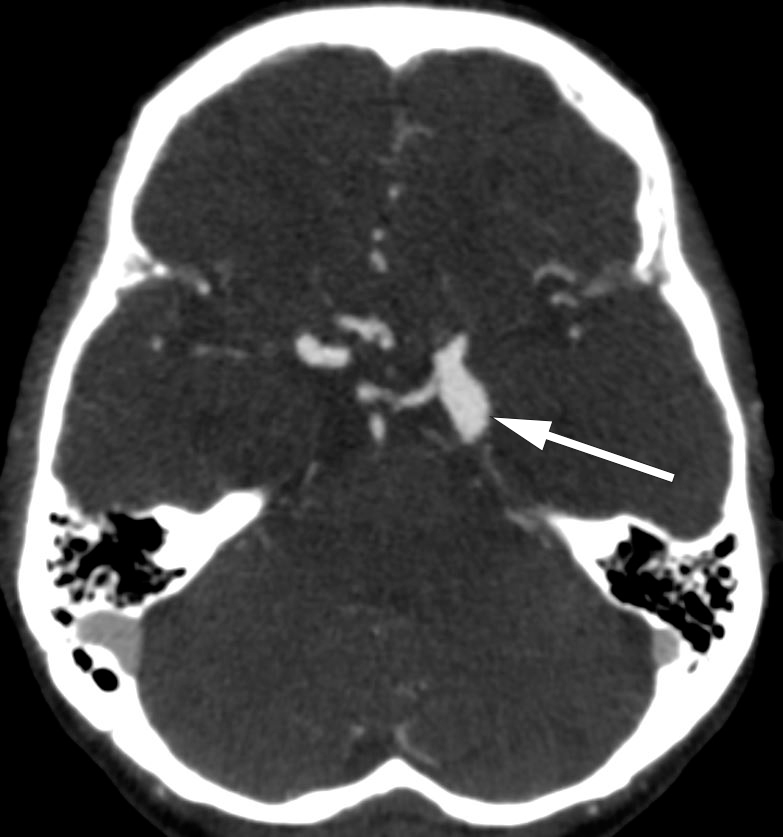

CT caput med angiografi gjort ved innleggelse viste vekst av det førstnevnte aneurismet til 15 x 9 mm. Nevrokirurgisk avdeling ble kontaktet på grunn av mistanke om truende ruptur, og det ble avtalt snarlig vurdering påfølgende morgen. Samme kveld fikk imidlertid pasienten hyperakutt bakhodepine med ledsagende nakkestivhet og hypertensjon, men ingen bevissthetsreduksjon. CT caput viste nytilkommet subaraknoidalblødning. Pasienten ble umiddelbart overflyttet til nevrokirurgisk avdeling hvor det ble utført kraniotomi og sikring med klipsligatur av det rumperte aneurismet. Pasienten overlevde, men fikk et betydelig nevrologisk sekvele.